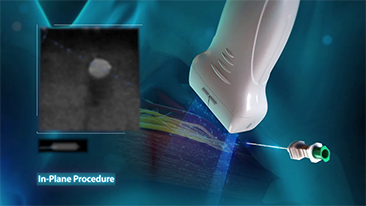

Due to the Coronavirus, hospitals and medical staff developed many new work practices. In acute settings this involved practices such as social distancing, personal protective equipment (PPE), rigorous handwashing, and disinfection of equipment every day.

Portable, highly mobile and versatile equipment came to the fore in point-of-care (POC) particularly when wards and operating theatres are spread across several floors and access to specialist devices is at a premium.